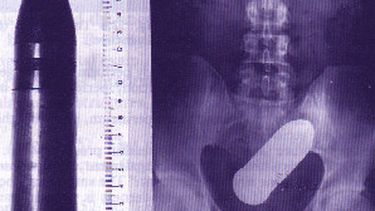

Accidentes sexuales que terminan en Urgencias